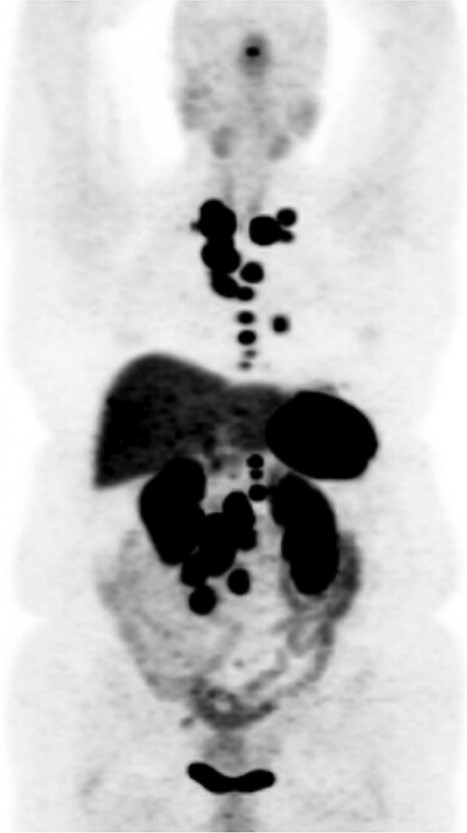

DOTATATE positron emission tomography-computed tomography scan at time of diagnosis in November 2017 revealed a small bowel primary tumor in the right lower quadrant consistent with terminal ileum (A) as well as the periduodenal mass near the root of the mesentery (B). Coronal reformatting redemonstrates the primary tumor (C) and mesenteric mass (D).